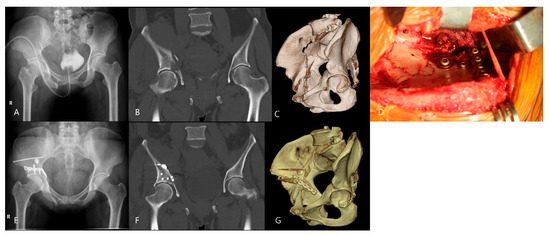

Compression Osteosynthesis Without Iliac Crest Osteotomy Through the Anterior Iliac Approach for Incomplete High Anterior Column Fractures of the Acetabulum: A Case Series and Surgical Technique

by Young-Ho Cho, Young-Soo Byun and Seong-Eun Byun

J. Clin. Med. 2026, 15(7), 2739; https://doi.org/10.3390/jcm15072739 - 4 Apr 2026

Introduction: An incomplete high anterior column fracture of the acetabulum is commonly considered to require completion of the fracture. However, reduction may become more difficult after completing the incomplete fracture due to plastic deformation. This study describes a surgical technique of compression osteosynthesis [...] Read more.

Introduction: An incomplete high anterior column fracture of the acetabulum is commonly considered to require completion of the fracture. However, reduction may become more difficult after completing the incomplete fracture due to plastic deformation. This study describes a surgical technique of compression osteosynthesis without completing the incomplete fracture and evaluates the clinical and radiographic outcomes. Materials and Methods: In this retrospective study, 25 patients with incomplete high anterior column fractures met the inclusion criteria. The fracture was reduced and stabilized by compression osteosynthesis through the anterior iliac approach without completing the incomplete fracture in the iliac wing. Patient demographics, the mechanism of injury, associated injuries, time to surgical reconstruction, operation time, and postoperative complications were analyzed. The quality of reduction and outcome were evaluated according to Matta’s criteria. Results: The mean operation time was 110 ± 23 min (range, 75–160). All fractures achieved bone union at a mean of 10.2 ± 1.4 weeks (range, 8–14). The quality of fracture reduction was graded as anatomical in 22 hips, imperfect in one and poor in two. Clinical results were excellent in 19 patients and good in six, and radiographic results were excellent in 22 patients and good in three. No statistically significant differences were observed between patients with and without quadrilateral plate fractures. Lateral femoral cutaneous nerve injury occurred in 13 patients (52%), mostly without significant symptoms. One patient experienced vascular injury. Conclusions: Incomplete high anterior column fractures can be effectively reduced and stabilized by compression osteosynthesis through the anterior iliac approach without completing the incomplete fracture in the iliac wing. This case series demonstrated favorable clinical and radiographic outcomes using this surgical technique. However, because this study was a retrospective case series with a small sample size and no comparative control group, further studies are required to confirm these findings. Full article